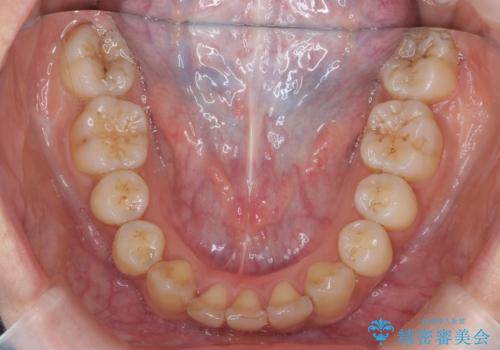

結果下の前歯一本抜歯ですみ、治療期間も想定よりも短く終わり、無事うまく治療することができました。

前歯の角度もよくなり、奥歯のかみ合わせも問題なく、上は非抜歯で口元も閉じやすくなりました。

下の前歯を1本の抜歯にしていますので上下の正中は合わない仕上がりとなっております。その代わり奥歯のかみ合わせと抜歯の本数削減を優先しています。